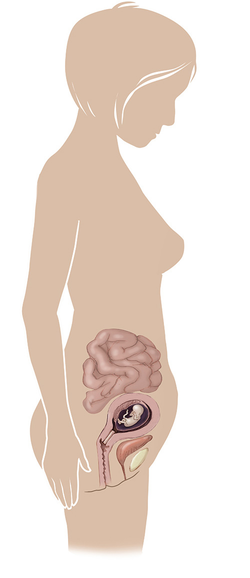

مراحل تطور الجنين أثناء الحمل

تطور الجنين خلال فترة الحمل على ثلاثة مراحل: أول 14 أسبوع من الحمل ، ثم تطوره بداية من الأسبوع 14 وحتى 28 أسبوعا ، ثم الثلث الأخير من 28 إلى 40 أسبوع من الحمل ... المزيد

مراحل تطور الحمل أسبوعيا بالصور

مراحل تطور الحمل أسبوعيا لكل من الأم والجنين داخل الرحم مدعومة بالصور التوضيحية ... المزيد